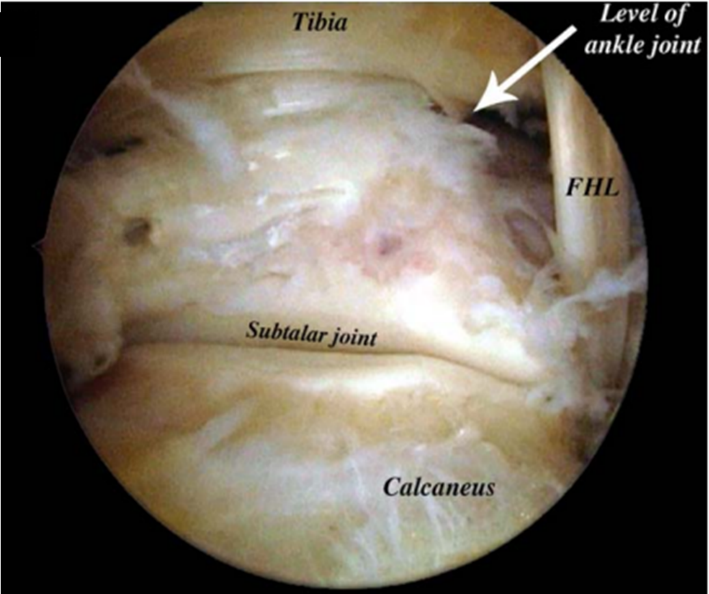

后踝关节镜手术